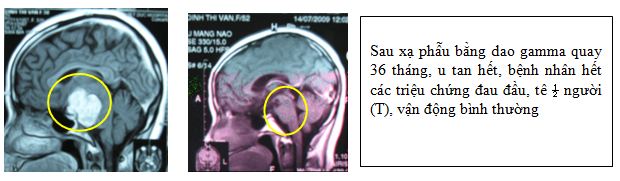

2. U màng não

Bệnh nhân Nguyễn Đ, T, nam, 32 tuổi

Chẩn đoán: U màng não

Chỉ định: xạ phẫu bằng dao gamma quay, liều 20 Gy